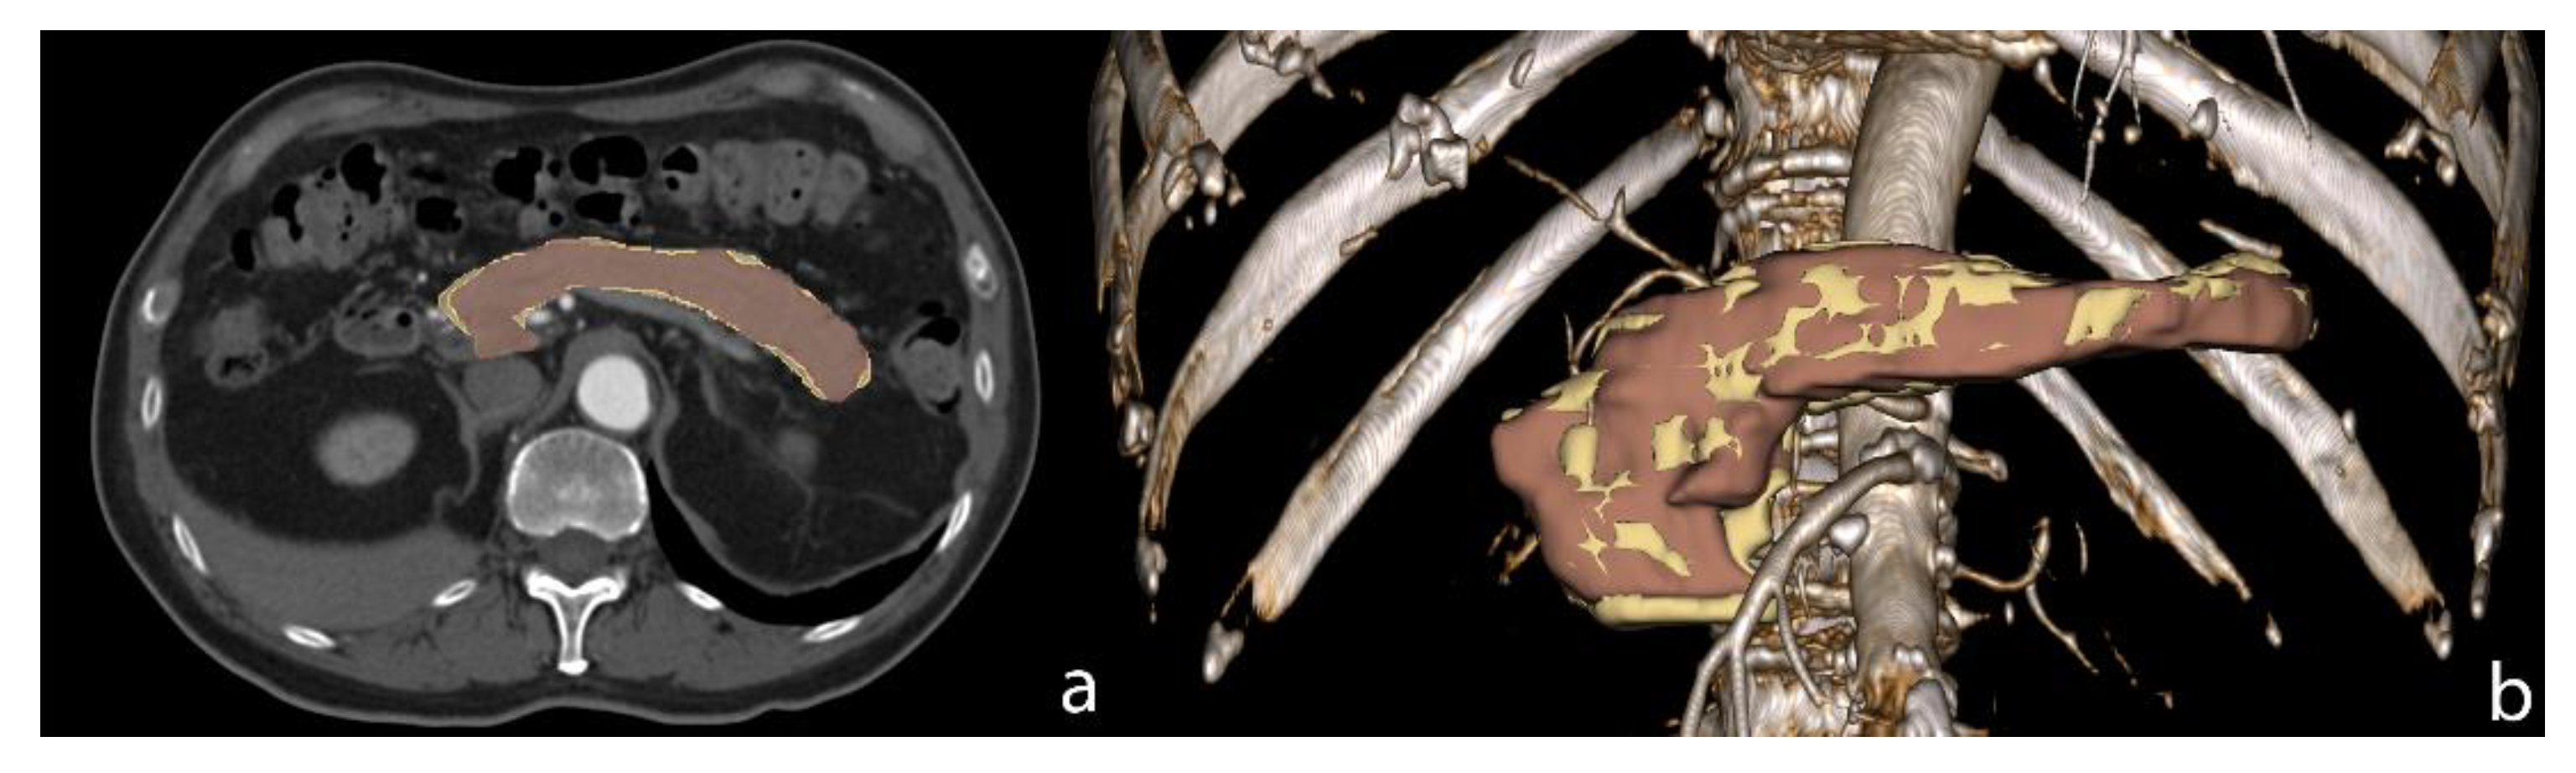

2. Segmentation